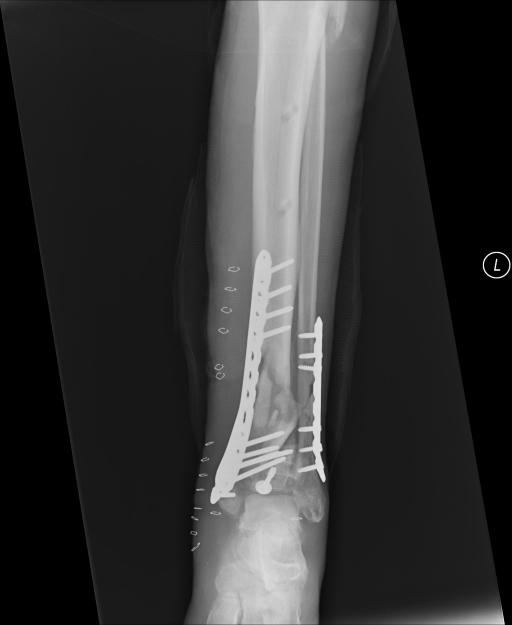

Post-corrective surgery X-Rays of the damaged right & left legs / ankles

The first two x-rays show Liam’s left ankle and pelvis prior to the accident. For comparison purposes it is interesting to see the

differences. The next x-rays were taken after the corrective surgery performed by Dr. Armendariz. Noticed that Dr. Armendariz has used tibia

bracing and also aligned the bone fragments of the left leg so that they could heal in the proper orientation. The external fixation has been

removed and Liam’s left foot has been returned to a more natural alignment.